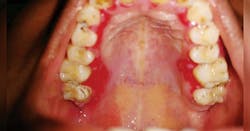

Figure 1: Palatal MMP. Courtesy of Dr. T.R. Gururaja Rao

Figure 1 depicts the palatal lingual gingiva with extreme redness. Figure 2 depicts the gingival areas in a patient with MMP with epithelial stripping around the margin of #7. Figure 3 depicts the scarring of the eye and symblepharon/entropion and adhesion of the eye.